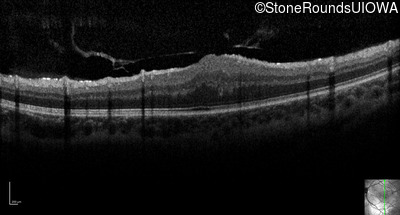

Optical Coherence Tomography - Right - 20/2000

Exemplar / OCT Stack